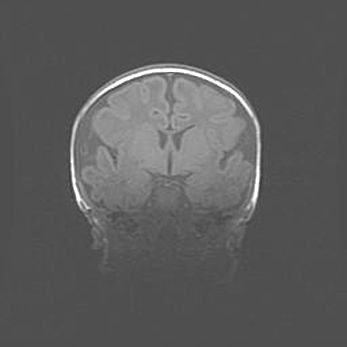

Открытая гидроцефалия.

Возраст: 9 месяцев 12 дней

Вес: 6800 г

Пол: мужской

Окружность головы: 41,5 см

Срок гестации: 28 недель

Гидроцефалия головного мозга у новорожденных имеет характерный признак: опережающий рост окружности головы приводит к визуально хорошо определяемой гидроцефальной форме сильно увеличенного в объёме черепа. Детские неврологи определяют следующие симптомы гидроцефалии у грудничков: выбухающий напряжённый родничок, частое запрокидывание головы, смещение глазных яблок к низу.